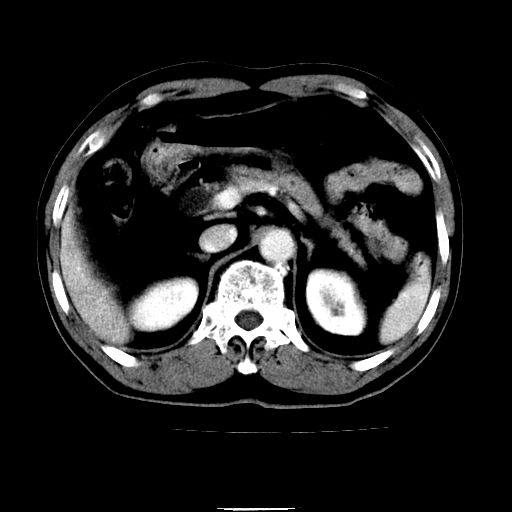

以下是引用chenqiong在2010-3-25 20:56:00的发言:[br]1、胆囊炎,胆囊息肉[br]2、肝内胆管及胆总管扩张,胆总管下端结石[br]3、十二指肠乳头旁憩室

以下是引用zxl51642在2010-3-26 10:47:00的发言:[br]胆囊炎,胆囊息肉,胆总管扩张,但未看到明显肿块,肝内胆管扩张不像恶性,炎性狭窄或阴性结石可能吧,建议mrcp,右肾小囊肿